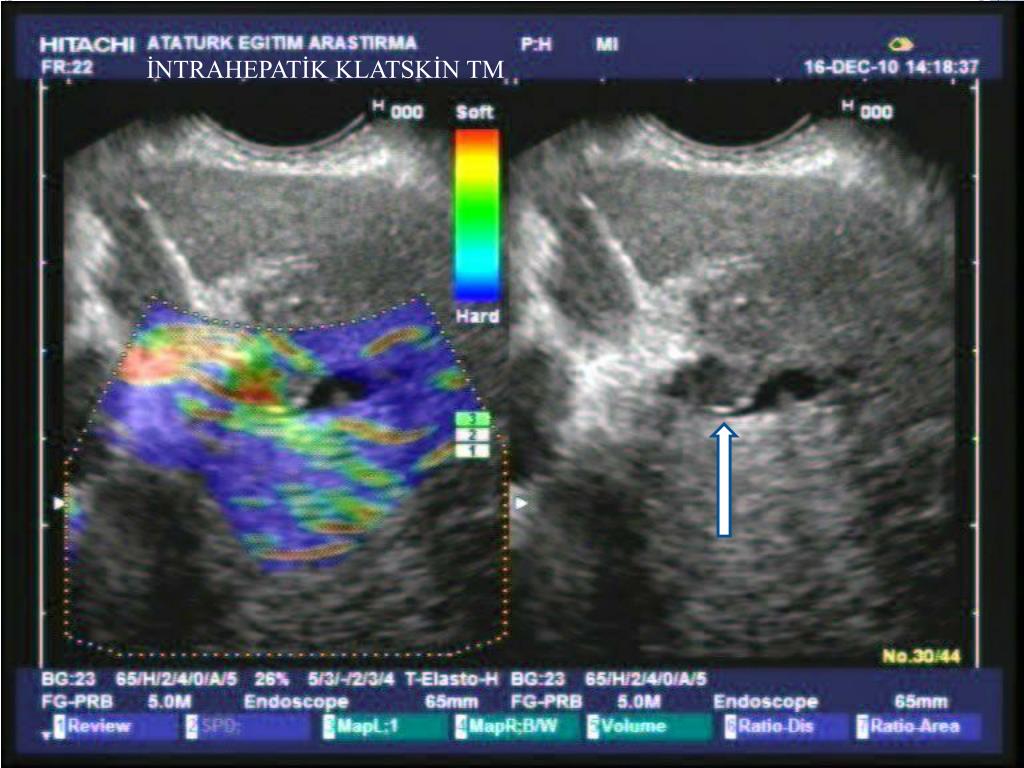

23. İNTRAHEPATİK KLATSKİN TM